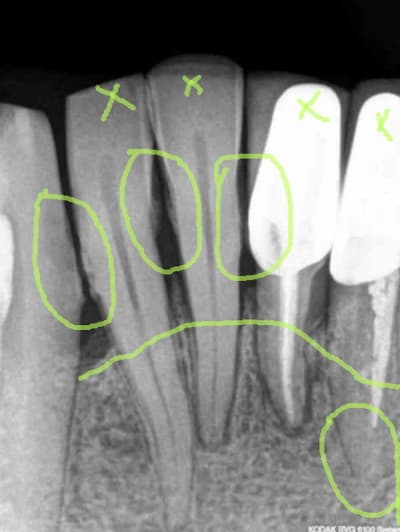

1)2)3) suite à de vilaines bactéries mangeuses d'apex (pas alapex, hein! lui il est immangeable) 31 est extraite 15 jours avant implantation.

4)j'aurai bien volontiers retiré 32 également mais le patient ne veut pas (pour l'instant).